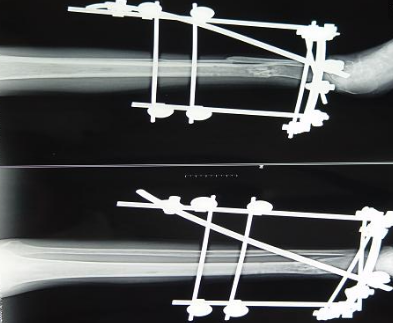

但是從實際應(yīng)用來看,碳纖維增強peek復(fù)合材料零部件所應(yīng)對的環(huán)境中腐蝕因素并非是重要的問題,這些零部件的機(jī)械性能相對更為重要。在此情況下,長纖碳纖維增強無疑是比短切碳纖維或粉末碳纖維的增強效果更好。我公司在汲取國外同行先進(jìn)制造經(jīng)驗的基礎(chǔ)上,在長纖碳纖維增強peek復(fù)合材料的應(yīng)用方面取得了很大的進(jìn)展,不僅通過工藝技術(shù)大幅度降低了長纖碳纖維增強peek的成本價格,而且其生產(chǎn)的長纖碳纖維增強peek復(fù)合材料骨外科用瞄準(zhǔn)器、瞄準(zhǔn)架、外固定支架等醫(yī)療器械零部件均已達(dá)到國際同類產(chǎn)品的質(zhì)量水準(zhǔn),打破了國內(nèi)以短切或粉末碳纖維peek復(fù)合材料為主的應(yīng)用格局,為碳纖維增強peek復(fù)合材料的應(yīng)用提供了更多的方向。